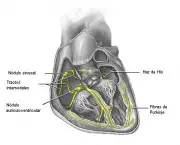

Em contraste a paragem cardíaca é causada por uma arritmia cardíaca súbita chamada fibrilação ventricular. Na fibrilação os sinais elétricos dentro do coração de repente se tornaram caóticos. Porque esses sinais elétricos controlar o tempo e a organização dos batimentos cardíacos, quando os símbolos degeneram para o caos total, o coração de repente pode parar. Ou seja, gera a “parada cardíaca”. O resultado comum é a morte súbita! O tratamento para a parada cardíaca é começar a ressuscitação cardiopulmonar imediata (CPR) para apoiar a circulação da vítima. Logo que possível é necessário entregar um grande choque elétrico ao coração com um dispositivo chamado “desfibrilador”. O grande choque permite que o sinal elétrico do coração se reorganizar para o órgão começar a bater de novo. Não se pode ignorar que a morte ocorre em poucos minutos de parada cardíaca, a menos que a ajuda de especialistas esteja disponível. Grande maioria dos indivíduos não é ressuscitada com sucesso. Parada cardíaca tende a ser comum em pessoas que têm vários tipos de doença cardíaca subjacente, um ataque cardíaco prévio ou qualquer condição que produz insuficiência cardíaca. De fato, pacientes que tiveram ataque cardíaco ou insuficiência cardíaca devem ser considerados para a inserção de um desfibrilador cardíaco implantável, aparelho que ressuscita automaticamente as pessoas que sofrem paradas cardíacas. Outras causas de paragem cardíaca incluem certas anomalias hereditárias que tendem a aumentar o risco de fibrilação ventricular e o uso de várias drogas (em especial cocaína). Se um parente próximo morreu é importante tentar saber a causa exata da morte. Seu risco de ataque cardíaco e de alguns tipos de parada cardíaca pode ser maior se um parente próximo experimentou os eventos. Certifique-se de obter o máximo de informações que puder.